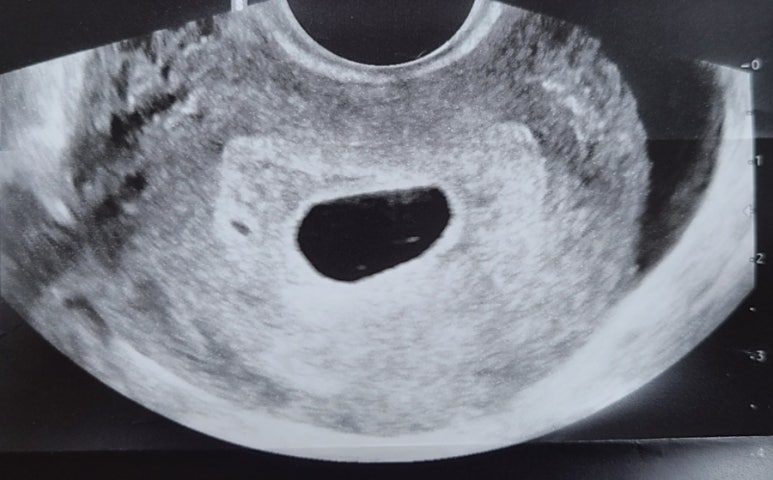

진료실에서 선생님께서는 초음파를 보기 시작하셨는데, 떨리는 마음으로 함께 모니터를 본 나는 뭔가 이상함을 느꼈다. 인터넷에서 본 다른 임산부들의 초음파 사진과는 확연히 달랐다. 분명 아기집이 크게 있는데 난황이 없었다.

나의 케이스는 '고사난자'라고도 하는 케이스인데, 초음파 상에 임신 낭(아기집)은 확인되지만 배아(태아)가 보이지 않는 경우이다. 들어보지도 못한 케이스라서 처음엔 부정했다. 다음 날 다른 산부인과에서 같은 판정을 받기 전까지는. 다른 산부인과에서도 빨리 소파술을 하지 않으면 임산부의 건강에도 안 좋은 영향을 미친다고 하셨다.

이렇게 예쁜 아기집을 만들어놓고 아기는 왜 오지 않았을까...?

오다가 잠시 길을 잃었나 보다.

다음번엔 길을 잃지 말고 잘 찾아오렴...